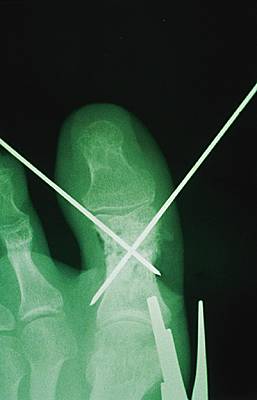

Procédé d'ostéosynthèse utilisant des broches (tiges métalliques) pour maintenir les fragments osseux d'une fracture, de façon temporaire ou définitive.

Le brochage est souvent utilisé dans la réparation des os de petite taille (main, pied et doigt) et pour le maintien de la réduction des fractures de l'extrémité inférieure du radius (poignet). Dans certains cas, il peut être utilisé comme contention temporaire d'une fracture avant installation d'une plaque ; les broches ont alors pour fonction de maintenir les fragments osseux en place et de faciliter ainsi l'ostéosynthèse.

Les broches sont des tiges métalliques droites et de section circulaire, rigides mais souples, de longueur et de diamètre variables. Elles peuvent être posées à l'aide d'un moteur rotatif, électrique ou à air comprimé, qui permet de perforer les os durs. Pour les petits os, le chirurgien recourt parfois à un « nez américain » (mandrin muni d'une poignée). Le brochage peut nécessiter plusieurs broches, notamment pour la réduction de fractures de l'humérus : on parle alors de brochage fasciculé.